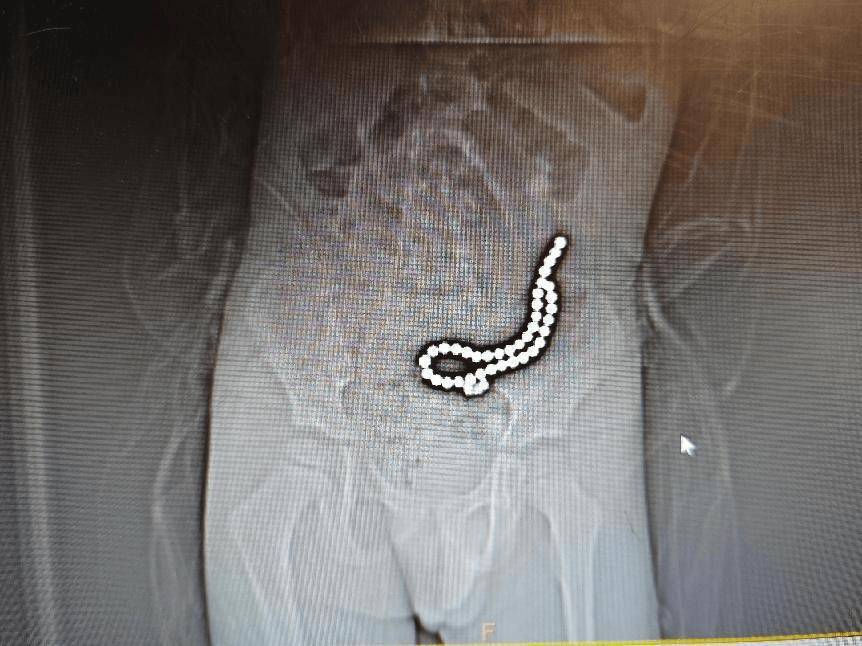

经过初步的影像学检查,医疗团队发现:病人体内竟然有37颗异物,连在一起呈手串状,并伴有小肠穿孔。

术前腹部DR片

面对如此严重的病情,丽江市人民医院普外一科立即启动了紧急救治程序,组织专家团队进行会诊,并制定出了周密的手术方案。但手术过程中,医疗团队发现了比预想中更为复杂的情况:病人小肠内的异物竟然是被称为无声“肠道杀手”的磁力珠。